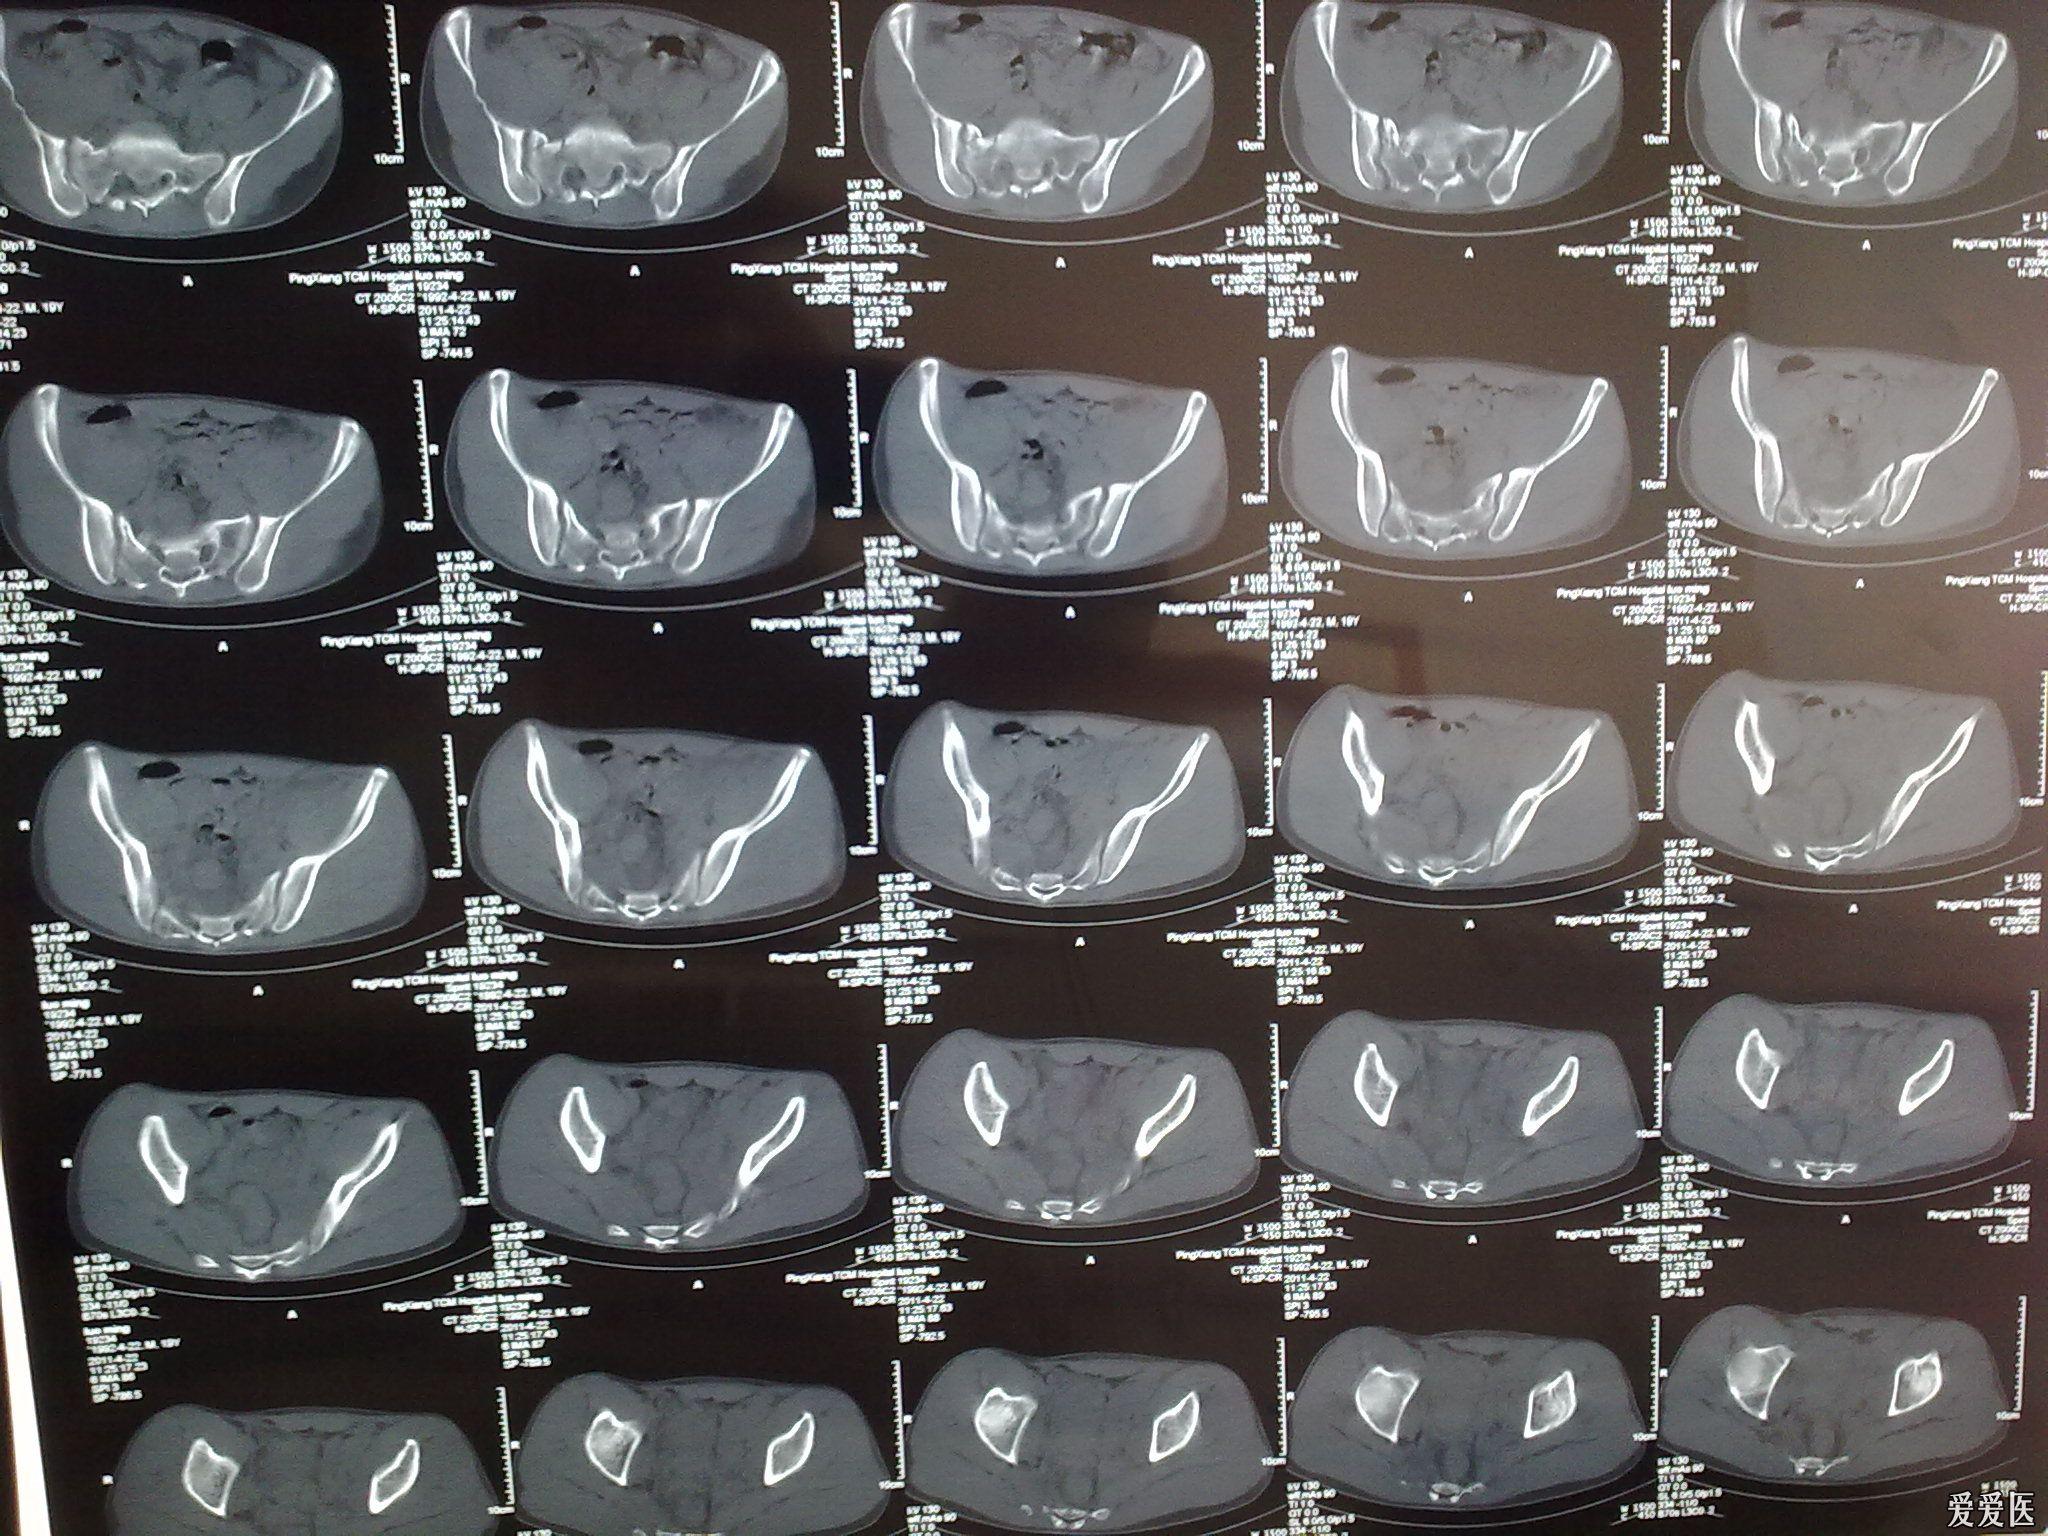

骨盆ct片高手阅片啊

图片尺寸2560x1920